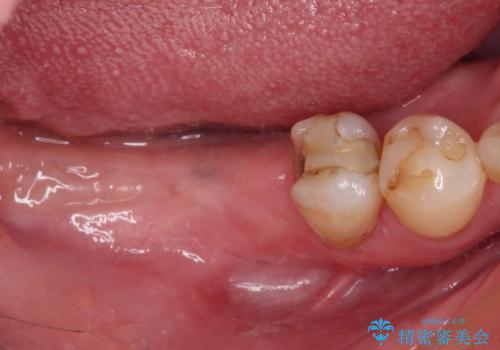

診察したところ、前歯は反対咬合であり、その影響で抜歯が必要な奥歯があることが分かりました。

抜歯が必要な奥歯は、インプラント並びにブリッジにより補綴を行い、上下前歯は反対咬合を改善させるように補綴治療を行うこととしました。